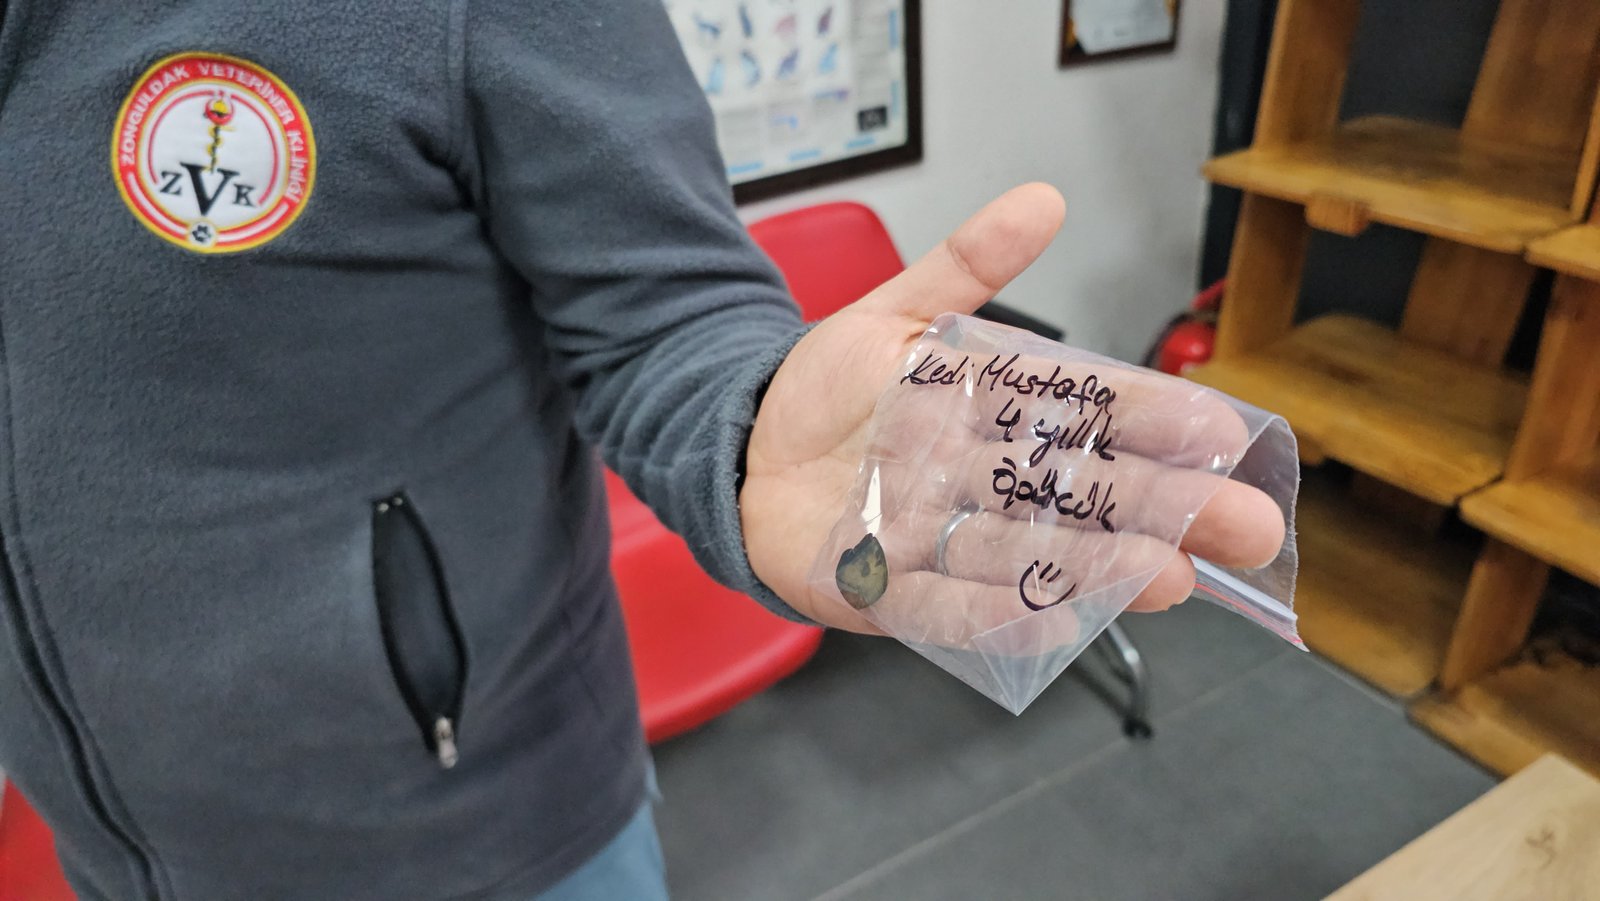

Zonguldak’ta, 5 yaşındaki ‘Mustafa’ isimli kedi 4 yıldır devam eden kusma şikayeti nedeniyle sahipleri tarafından özel bir veteriner kliniğe götürüldü. Burada tomografi çekilen kedinin midesinde dolap veya camlara yapıştırılan vantuzlardan biri olduğu tespit edildi. Endoskopi yöntemiyle vantuz, kedinin midesinden çıkarıldı. Yapılan gözlemde kedinin kusma şikayetinin geçtiği anlaşılınca sahibine teslim edildi. Vantuzun mideye verdiği zarar nedeniyle de ilaç tedavisine başlandı.

Operasyonu yürüten Veteriner Hekim Ömer Faruk Alkan, yerde bırakılan toka, ip gibi küçük nesnelerin kedi sahipleri için dikkat edilmesi gereken şeylerden olduğunu belirterek, “4 yıldır kusmasına sonuç, cevap alınamamıştı. Röntgenlerde hiçbir sıkıntı yoktu, bütün testleri çok iyiydi. Hiçbir problemi yoktu ama 2 günde 1 kusma şikayeti vardı. Çektiğimiz tomografide, çocuğun midesinde 4 yıldan beri kalan buzdolabı yapışkanlarından vantuzlarından olduğunu gördük. Ameliyatsız bir şekilde, endoskopi ile mideden çıkarttık. Şu an kusması tamamen kesildi. Herhangi bir kusmamız yok. Çocuk 4 yıl sonra ilk kez kusmadığı 2 günü arka arkaya yaşadı. Kusmayacak gibi gözüküyor. Burada vantuzun mideye verdiği zararlar var, mide duvarında kalınlaşma gibi onların tedavisini yapacağız. İnşallah Mustafa bundan sonraki hayatına kusmadan devam edecek. Mustafa 5 yaşında, 1 yaşından beri kusuyor. Yavruyken yemiş. Kedi sahipleri için de en önemli kısım bu, yerde toka, ip bu şekilde vantuz bulundurmamaları gerekiyor. Kedi yiyebiliyor. Mustafa şanslı olanlardan, bağırsaklarına inmemiş tıkama yapmamış. Bağırsaklara inip tıkama yaptığında daha ciddi komplikasyonlara, ölüme sebep olabiliyor” dedi. (DHA)